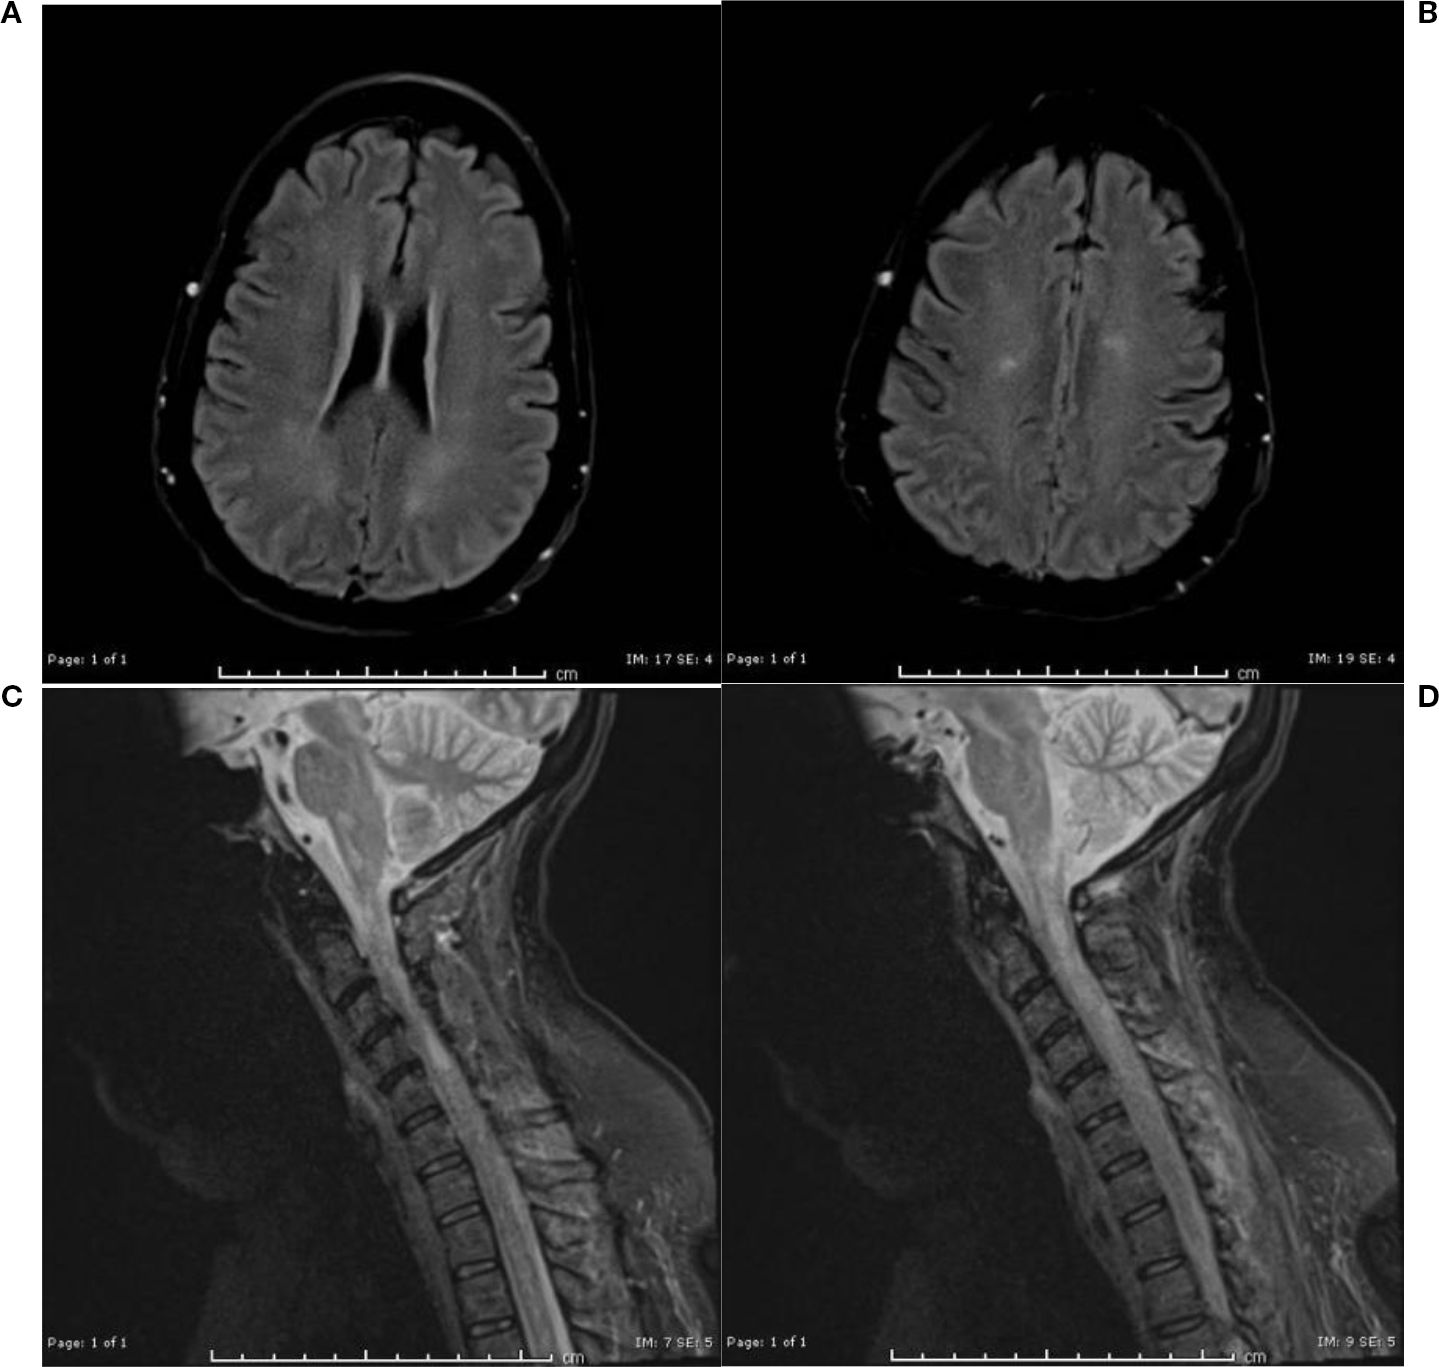

In June 2024, the patient received one cycle of polatuzumab vedotin 1.8 mg/kg as a bridge to CAR-T. CT showed para-aortic lymphadenopathy (7.2 cm). After T-cell collection, the patient received 3000 cGY in 10 fractions to the para-aortic nodes. Pre-CAR-T MRI brain was normal. On day -5 (5 days before CAR-T cell infusion), lymphodepleting chemotherapy was started. In September 2024, the patient received CAR-T with Axicabtagene ciloleucel. On day 0, ICE score was 10 and Keppra 750 mg BID was started as seizure prophylaxis. On day +1, she developed grade 1 CRS, treated with a dose of Tociluzumab for persistent grade I CRS. She required a second dose of tocilizumab on day +4 for persistent CRS. By day +5, her mental status declined (ICE score 1), prompting initiation of steroids (10mg of IV dexamethasone Q 6 hr, later escalated to IV methylprednisolone 1g daily). Given steroid-refractory grade 3 ICANS, Anakinra was also started (50 mg every 6 hours from days +5–10, increased to 300 mg TID on days +10–12, tapered to 200 mg BID on day +13, and 100 mg BID on days +14–15). On day +7, she received two additional doses of tocilizumab (a total of four doses; 680mg in IV 0.9% NaCl) for concurrent CRS with neurotoxicity. The patient developed myopathy and flaccidity of extremities on day +9 (ICANS grade 2). On day +10, the patient had acute onset asymmetrical pupils, and MRI of the brain revealed multiple medullary diffusion restrictions. At that time, the patient developed paraplegia. A lumbar puncture (LP) on day +12 demonstrated elevated protein and methylprednisolone was switched back to IV dexamethasone 10 mg every 6 hours An MRI on day +13 showed encephalopathy and possible immune-mediated demyelination (ICANS grade 3). Repeat MRI on day 14+ showed worsening edema and inflammation (Figures 1a–d), suggesting autoimmune demyelination. Despite steroids and anakinra, the patient’s symptoms persisted. A repeat LP was performed on day +15 for a more thorough workup; CSF flow and cytology was negative for malignant cells, all infectious workup in CSF was negative including adenovirus, HSV, culture/gram stain, and bacterial meningoencephalitis panel. On Day +15, methylprednisolone was restarted, and then transitioned to dexamethasone on day +17, which was then tapered to prednisone 5mg QD on day +19.

Figure 1. (a, b) MRI brain without contrast day 14+: Redemonstration of multiple foci of restricted diffusion in the lower medulla oblongata and the cervicomedullary junction. (c, d) MRI Cervical spine without contrast day 14: more conspicuous foci of T2/STIR hyperintensities scattered in the cervical cord, predominantly along the lateral columns of the cervical and upper thoracic cord, with corresponding associated restricted diffusion.